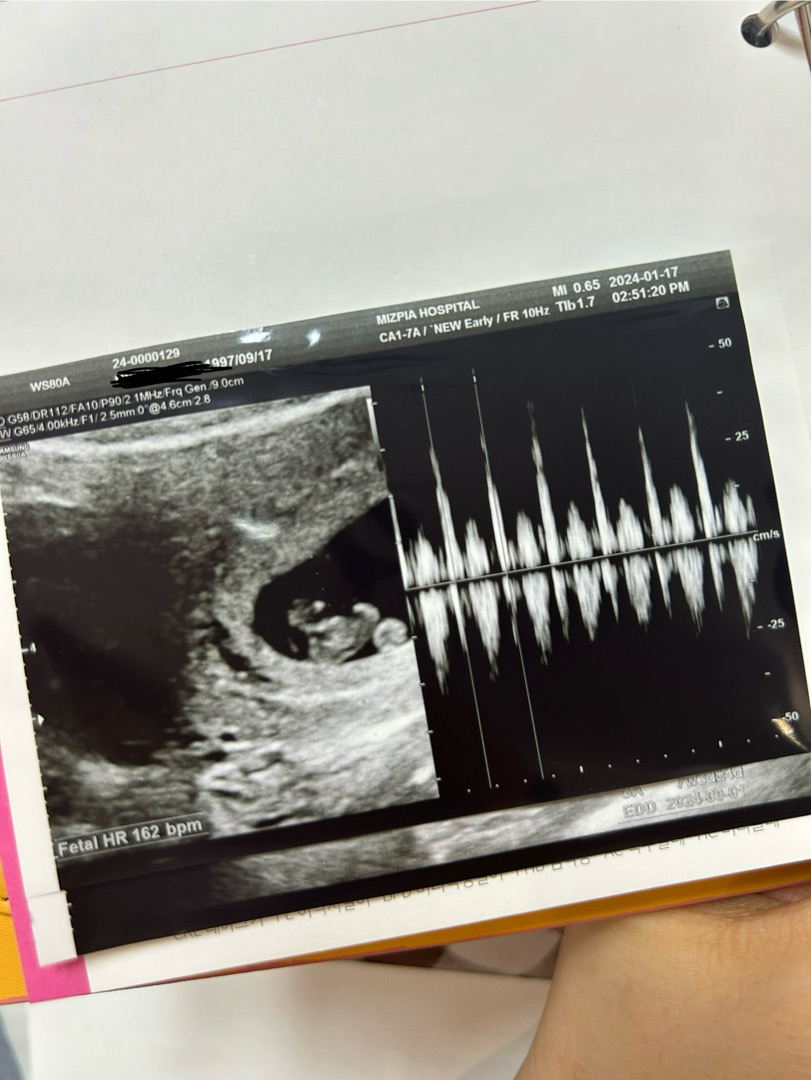

7주 4일차 인줄 알았는데 7주3일로되어 하루차이로 다시 9월 베동으로 왔네욤ㅎㅎ 아기는 주수에 맞게 1.19cm에 심장소리도 우렁차게 162bpm나왔어용ㅎㅎ🥰 기다리는 2주동안 입덧이 너무 힘들었지만 이렇게 무럭무럭 자라있는걸 보니 싹 나아지는 기분이네요😆 언능 안정기되서 입덧,토덧 좀 사라지면 좋겠어용ㅠ.ㅠㅠ